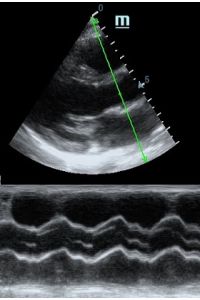

Оценка сокращения сегментов левого желудочка на глаз постепенно уходит в прошлое. Если в приборе нет функции радиального или лонгитудинального стрейна, на помощь опять может прийти Free Xros. Утолщение более 5 мм в систолу – нормальное сокращение, 2-5 мм гипокинез, истончение в систолу – дискинез.